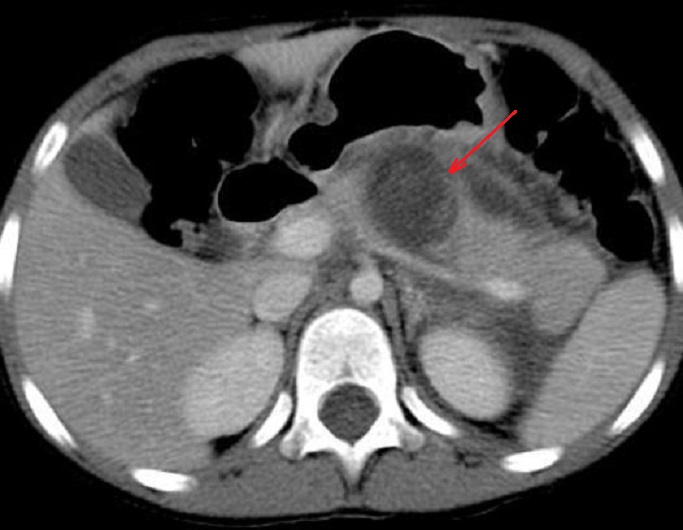

Image radiologique TDM de

contusion de la tete du pancreas avec de

elargir , heterogene a hypodense du pancreas avec un

epanchement liquidien peri-pre pancreatique ( fleche

rouge }. Coupe axiale TDM |